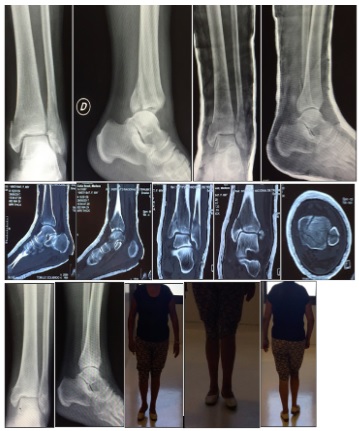

Figura 3: Luxofractura trimaleolar. Reducción en urgencias. Valoración con TAC de tobillo. Tratamiento ortopédico. Seguimiento al año, AOFAS=90

La evidencia no es suficiente para fijar todos los MP, hay que tener en cuenta múltiples factores como son: inestabilidad tibiotalar y sindesmótica comprobada, características morfológicas del MP y congruencias articulares (Figura 3).

En la revisión observamos como el tratamiento quirúrgico de las fracturas de MP en las fracturas bi-trimaleolares está mostrando buenos resultados funcionales con bajo índice de complicaciones. La reducción abierta y fijación interna con placa de sostén es el tratamiento que ha demostrado mejores resultados a corto y mediano plazo, no encontrando estudios con seguimiento a largo plazo.